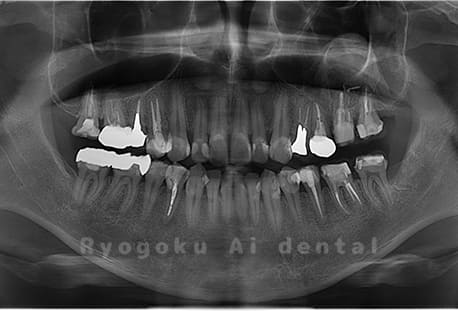

Case03

- 原因

- 上顎、下顎の親知らず

- 治療内容

- 上下4本の親知らずを抜歯したケースです。

<リスク・副作用>

手術後は痛み、腫れ、痺れなどの副作用が生じる場合があります。